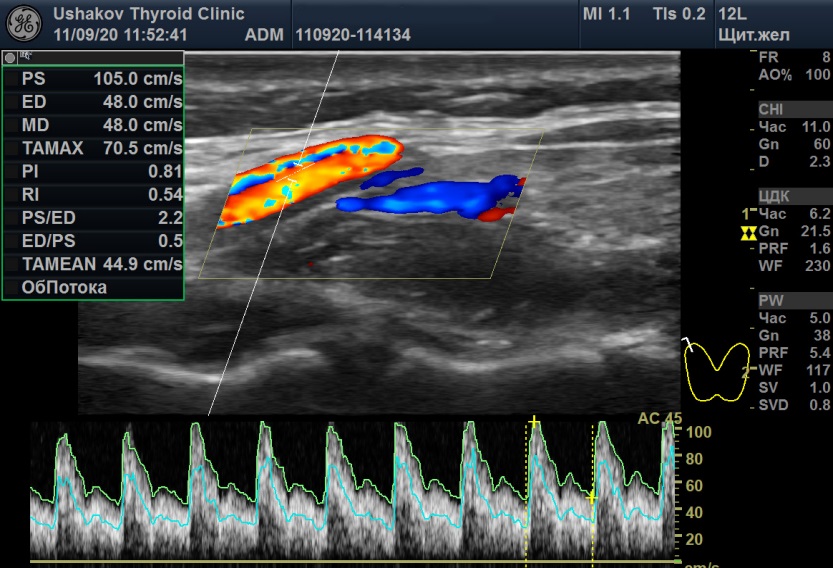

Рисунок 7 Максимальная пиковая скорость крови в верхних правой и левой артериях щитовидной железы пациентки С., 22 года. А – 04.08.20 в правой артерии ПССК 59,9 см/с, Б – 11.09.20 в правой артерии ПССК 105 см/с.

Избыточная нервная стимуляция ЩЖ отразилась также на изменении ПССК при допплерографии (

рис. 7). Максимальная ПССК в правой артерии увеличилась с 59,9 см/с (04.08.20)

до 105 см/с (11.09.20), а в левой – с 40,4 см/с (04.08.20), до 62 см/с (11.09.20). Эти большие значения ПССК (особенно 105 см/с) характерны для гипертиреоза и указывают на проводниковую нервную стимуляцию тиреоидной сосудистой сети вместе с усилением напряжения ткани щитовидной железы.